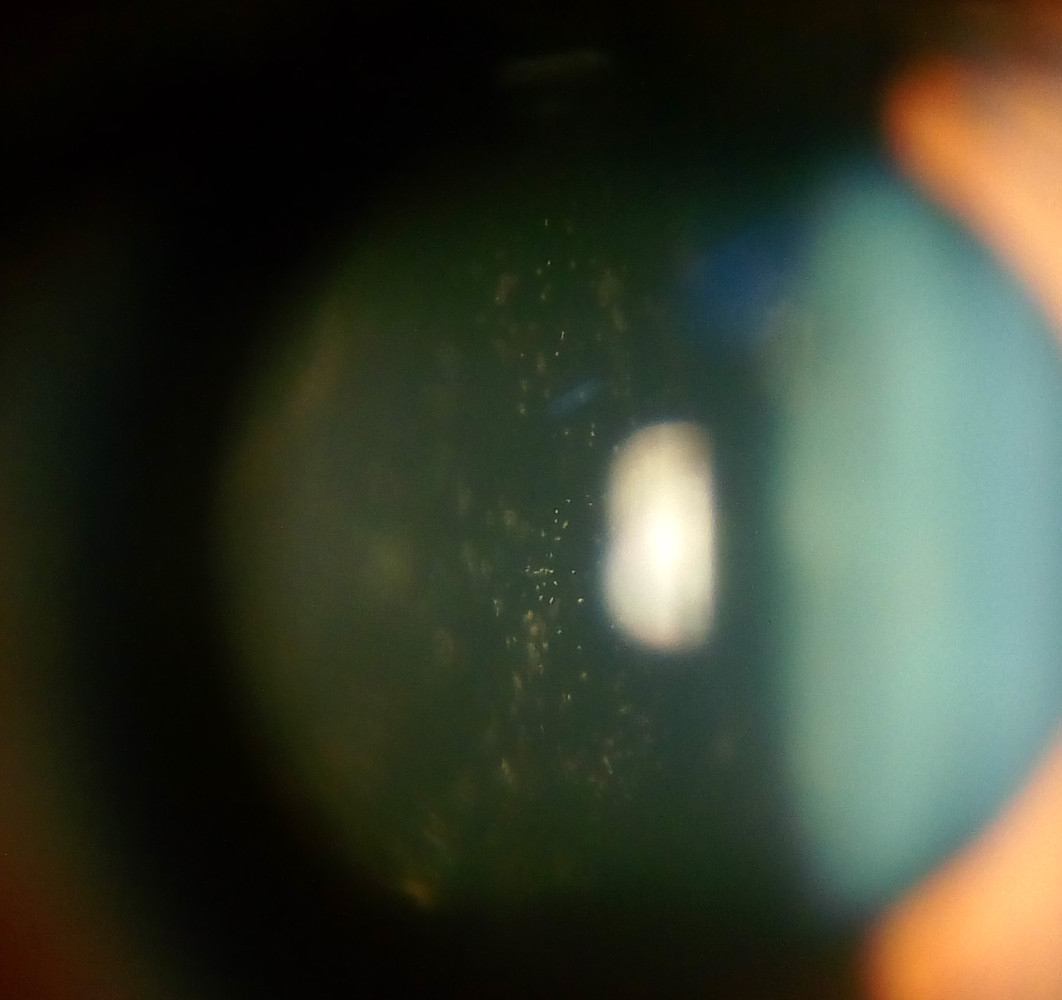

Uveitis is an inflammation of the middle structures of the eye (the uvea). Uveitis may be caused by a variety of different problems ranging from traumatic injury to autoimmune disease. Autoimmune uveitis is a serious health issue that can lead to blindness within a very short period of time if it isn't treated promptly. Dimethylsulfoxide (DMSO) and Chlorine Dioxide Solution (also known as Miracle Mineral Solution) are an important cure for autoimmune uveitis that can be used together, though they should be used at separate times when administering these medicines as eye drops. Both DMSO and Chlorine Dioxide Solution can be administered orally as well.

Another serious eye disorder that responds very well to treatment with B vitamins is cataracts. Riboflavin is vitamin B3 and it can be administered as eye drops. Oclumed is a blend of several detoxifying nutrients along with riboflavin that can be used to prevent and treat cataracts.